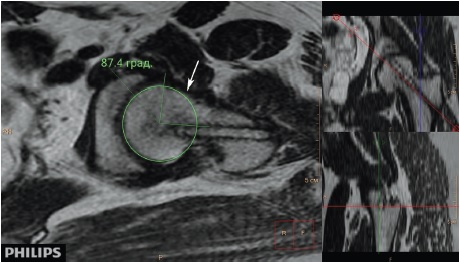

Рис. 3. МРТ левого тазобедренного сустава пациентки 18 лет 2 мес. через 4 года 7 мес. после операции, косая аксиальная проекция, Т2-взвешенное изображение. Деформация перехода «головка – шейка» (обозначена стрелкой) — отсутствие нормальной вогнутости перехода и увеличенный передневерхний угол α — 87,4 °